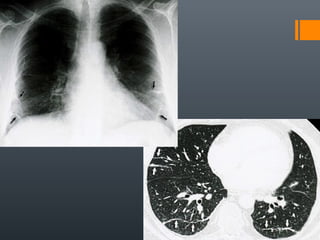

O documento discute vários conceitos radiológicos incluindo consolidação, atelectasia, nódulos, pseudocavidades e padrões intersticiais, fornecendo definições, sinais e diagnósticos diferenciais para cada tópico. Ele também discute a redução da atenuação pulmonar e fornece um link para mais informações.